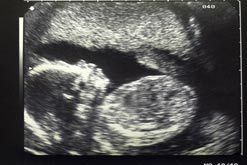

Baby scans: do we need them?28th Aug 2007

Ultrasound scans have become almost standard for pregnant women. But are they really justified?

For a large number of pregnant women, the scan which shows their unborn baby wriggling its feet and sucking its thumb is one of the most important milestones. But Hylton Meire, an eminent radiologist, has started a debate on whether the scans are really justified. Writing in the journal Ultrasound, Dr Meire argues that not only is there scant scientific evidence to prove that the 20 week scan is worth doing, he also questions the reliability of the standard method of testing for Down’s Syndrome – the nuchal fold measurement – which is taken during the earlier, 12 week scan. But is there value in knowing, in advance, if there is a risk of abnormality for your unborn child? And how can parents be supported through the difficult decisions if a risk is identified?